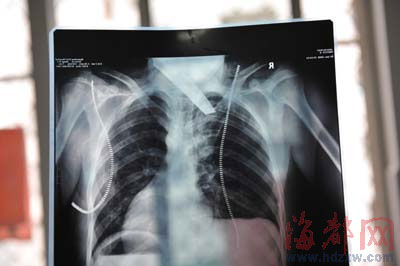

楊女士說,小勇當時在工廠外的一網吧上網,一名男子突然沖進來,幾乎沒說話,拿出一把長約20厘米的匕首,就朝小勇后背連捅兩下。要命的是,最后一刀從小勇右側后背猛插下去,插入小勇體內長10多厘米,傷及內臟,之后男子發現連刀都拔不出來,才沒再捅,逃出網吧。隨后,120急救醫生趕來,將倒在血泊中的小勇送到泉州市第一醫院急救。

前晚,在第一醫院急救室,經過4個多小時的搶救,醫生將匕首從小勇身上取出,發現這把匕首的刀尖扎斷了1厘米。由于小勇肺部被刺中,昨天上午,醫生再次進行了3個多小時的手術,切除了受傷的部分肺,直到下午,小勇才挺過來。“挺了一夜,現在總算醒了過來。”楊女士一夜沒睡,守在手術室外7個多小時,生怕兒子再醒不過來。不過,由于傷勢嚴重,小勇目前戴著氧氣呼吸,仍未脫險。